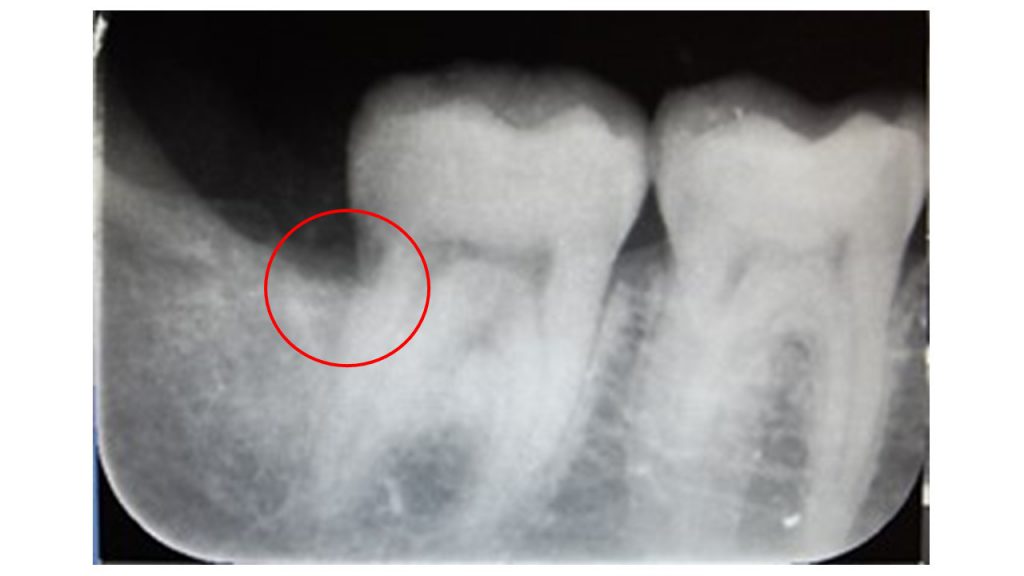

虫歯

【症例】コンポジットレジンを使用した保険診療での金属を使わない虫歯治療